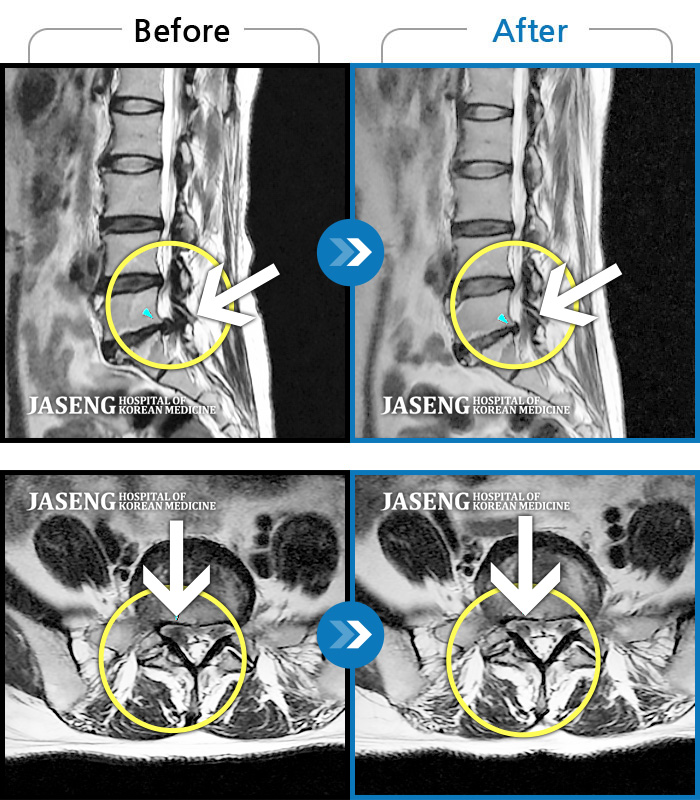

허리디스크

보라매 · 왕오호 원장

허리와 좌측 엉치 통증

촬영시기

2015.12.29 ~ 2018.10.11

2018.12.28